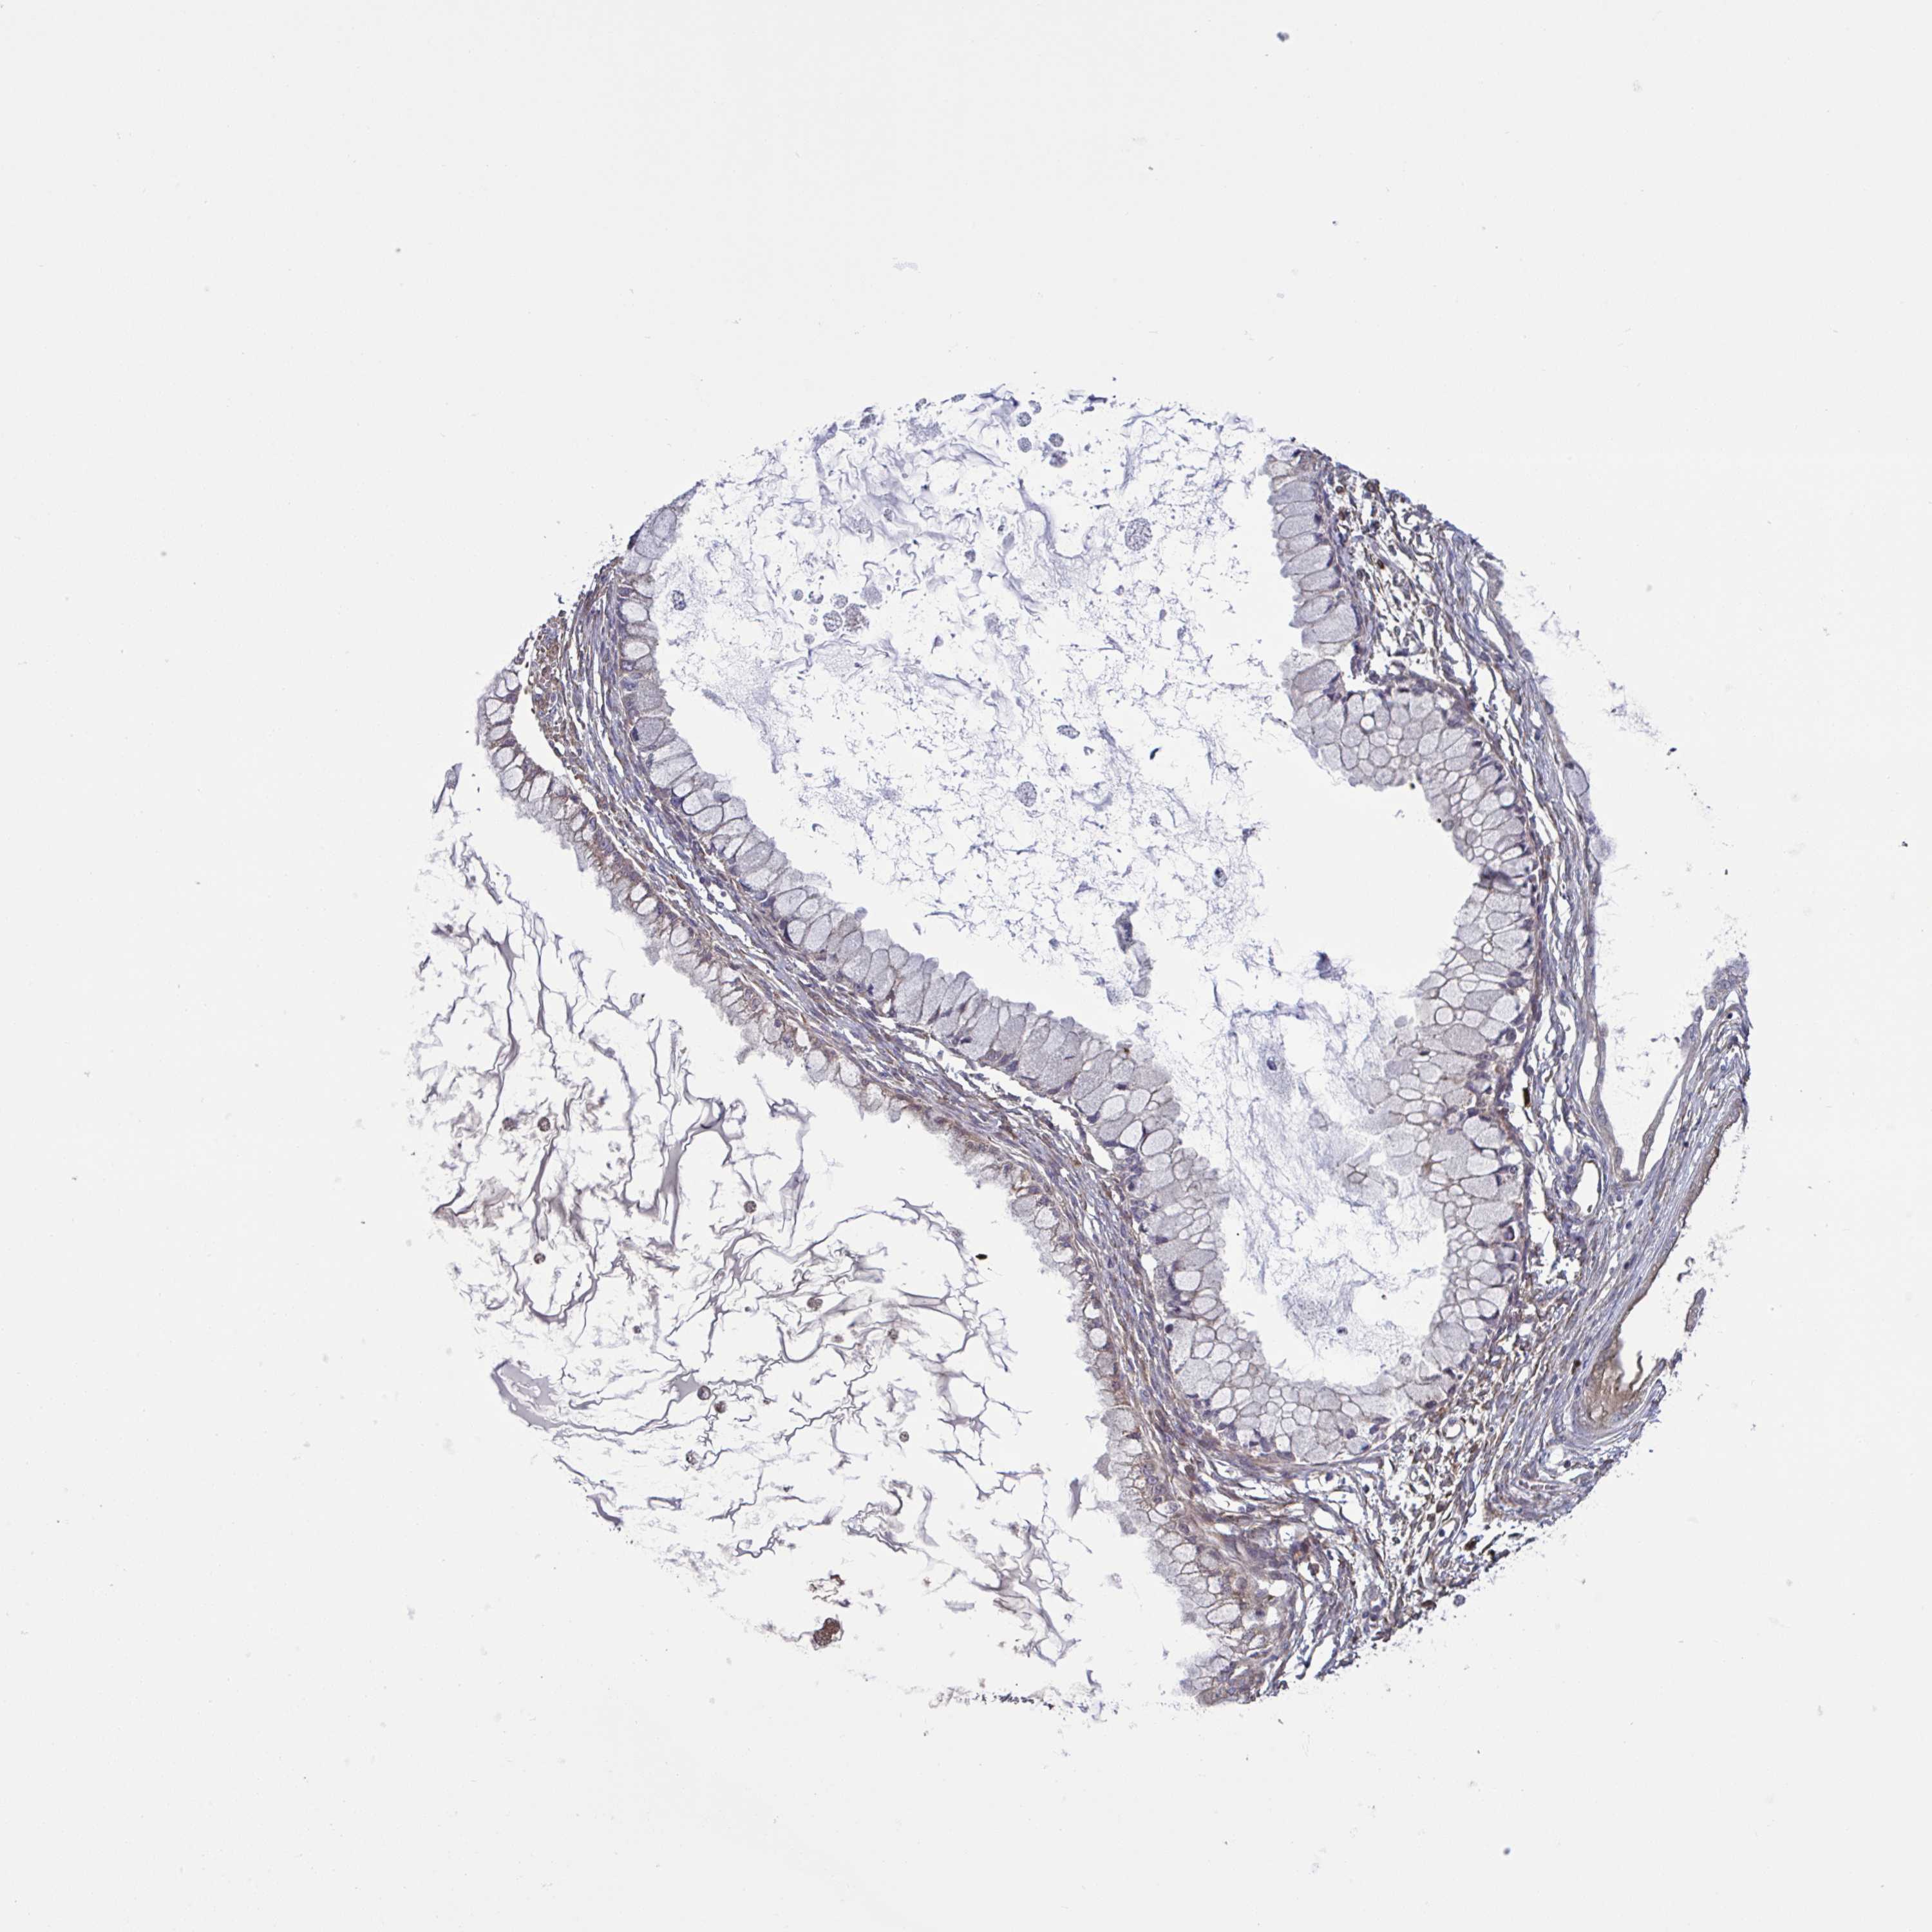

OVARIAN CANCER - Protein expressioni

A mouse-over function shows sample information and annotation data. Click on an image to view it in a full screen mode. Samples can be filtered based on level of antibody staining by selecting one or several of the following categories: high, medium, low and not detected. The assay and annotation is described here.

Note that samples used for immunohistochemistry by the Human Protein Atlas do not correspond to samples in the TCGA dataset.

Antibody stainingi

Antibody staining in the annotated cell types in the current human tissue is reported as not detected, low, medium, or high, based on conventional immunohistochemistry profiling in selected tissues. This score is based on the combination of the staining intensity and fraction of stained cells.

Each image is clickable and will lead to virtual microscopy that enables deeper exploration of all samples and also displays staining intensity scores, fraction scores and subcellular localization as well as patient and tissue information for each sample.

Antibody HPA058258

Cystadenocarcinoma, serous, NOS

Cystadenocarcinoma, mucinous, NOS

Carcinoma, endometroid